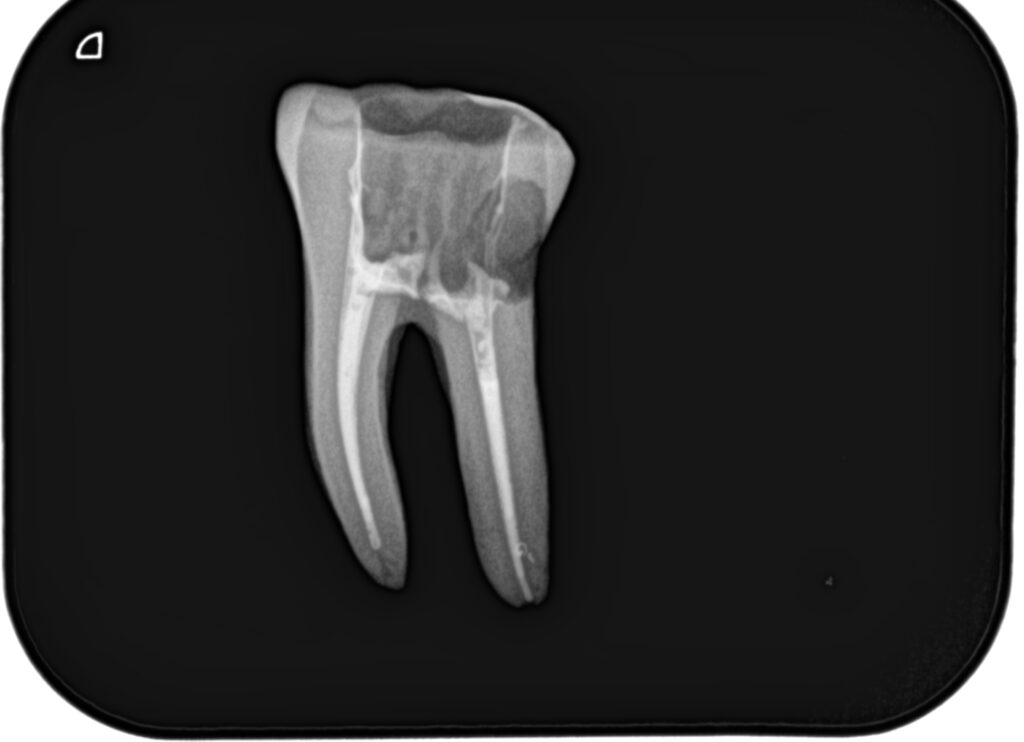

根管形成が終了すれば、根管充填だ。

その際に必要な物品は以下である。

日曜日は実習を行った。

土曜日の内容を投影した実習であった。

2本の歯牙で実習し、あっという間に1日は終了した。